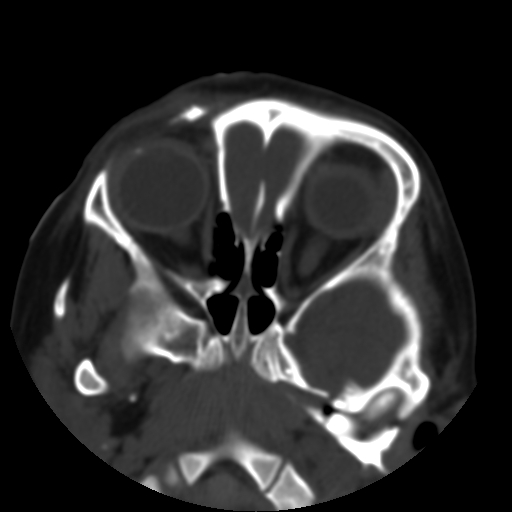

以下是引用深泽交通医院在2009-10-16 8:25:00的发言:[br]右眼环出血伴异物

以下是引用卜一在2009-10-16 15:01:00的发言:[br]右眼球挫裂伤伴异物!

以下是引用拾荒者在2009-10-17 18:38:00的发言:[br]鼻面部皮下积气,右侧睑缘及眼球壁高密度异物影,左侧眼球壁晶状体内侧缘处是圆形低密度影。低密度异物?应提请眼科医生注意。